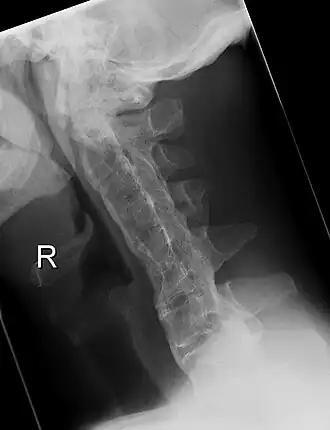

Röntgenfoto van de halswervelkolom met de ziekte van Bechterew in een ver gevorderd stadium. Duidelijk is te zien dat de wervels aan elkaar zijn vastgegroeid, de zogenaamde 'bamboo-spine'. | ||||

De wervelkolom kan na verloop van tijd in een benige zuil veranderen. Dit geeft op een röntgenfoto uiteindelijk een karakteristiek beeld, de zgn. 'bamboo-spine'. Daarom moet iemand met deze ziekte dagelijks oefenen om de rug zo veel mogelijk beweeglijk en in ieder geval recht te houden. Gebeurt dit niet, dan zullen de meeste lijders uiteindelijk geheel kromgroeien, waardoor ze op latere leeftijd nog slechts met moeite naar voren kunnen kijken.